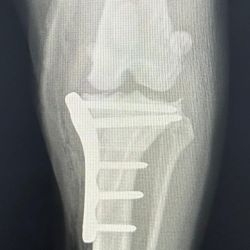

Chirurgie orthopédique et traumatologique

Chirurgie du genou, TPLO